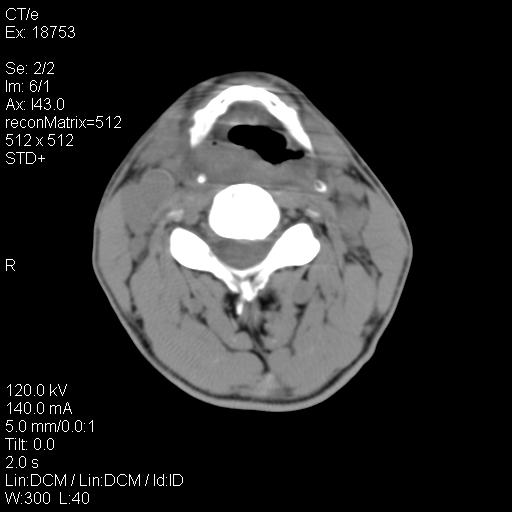

标题: CT21693:男 58岁 右侧咽部疼她2天余 PE:右侧扁桃体肿大 压痛 [打印本页]

标题: CT21693:男 58岁 右侧咽部疼她2天余 PE:右侧扁桃体肿大 压痛

1 弥漫性肿胀,与周围组织分界清晰,发病急,有明显症状,考虑急性炎症【wbc]

弥漫性肿胀,与周围组织分界不清,发病急,有明显症状,考虑:感染性病变!

右化脓性扁桃体炎症伴咽后壁脓肿形成.